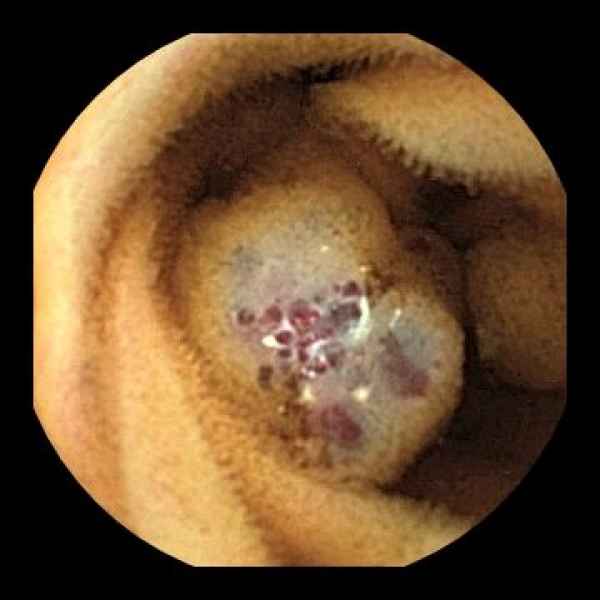

Cavernous hemangioma of the sigmoid colon : a rare cause of rectal bleeding

Fotografias